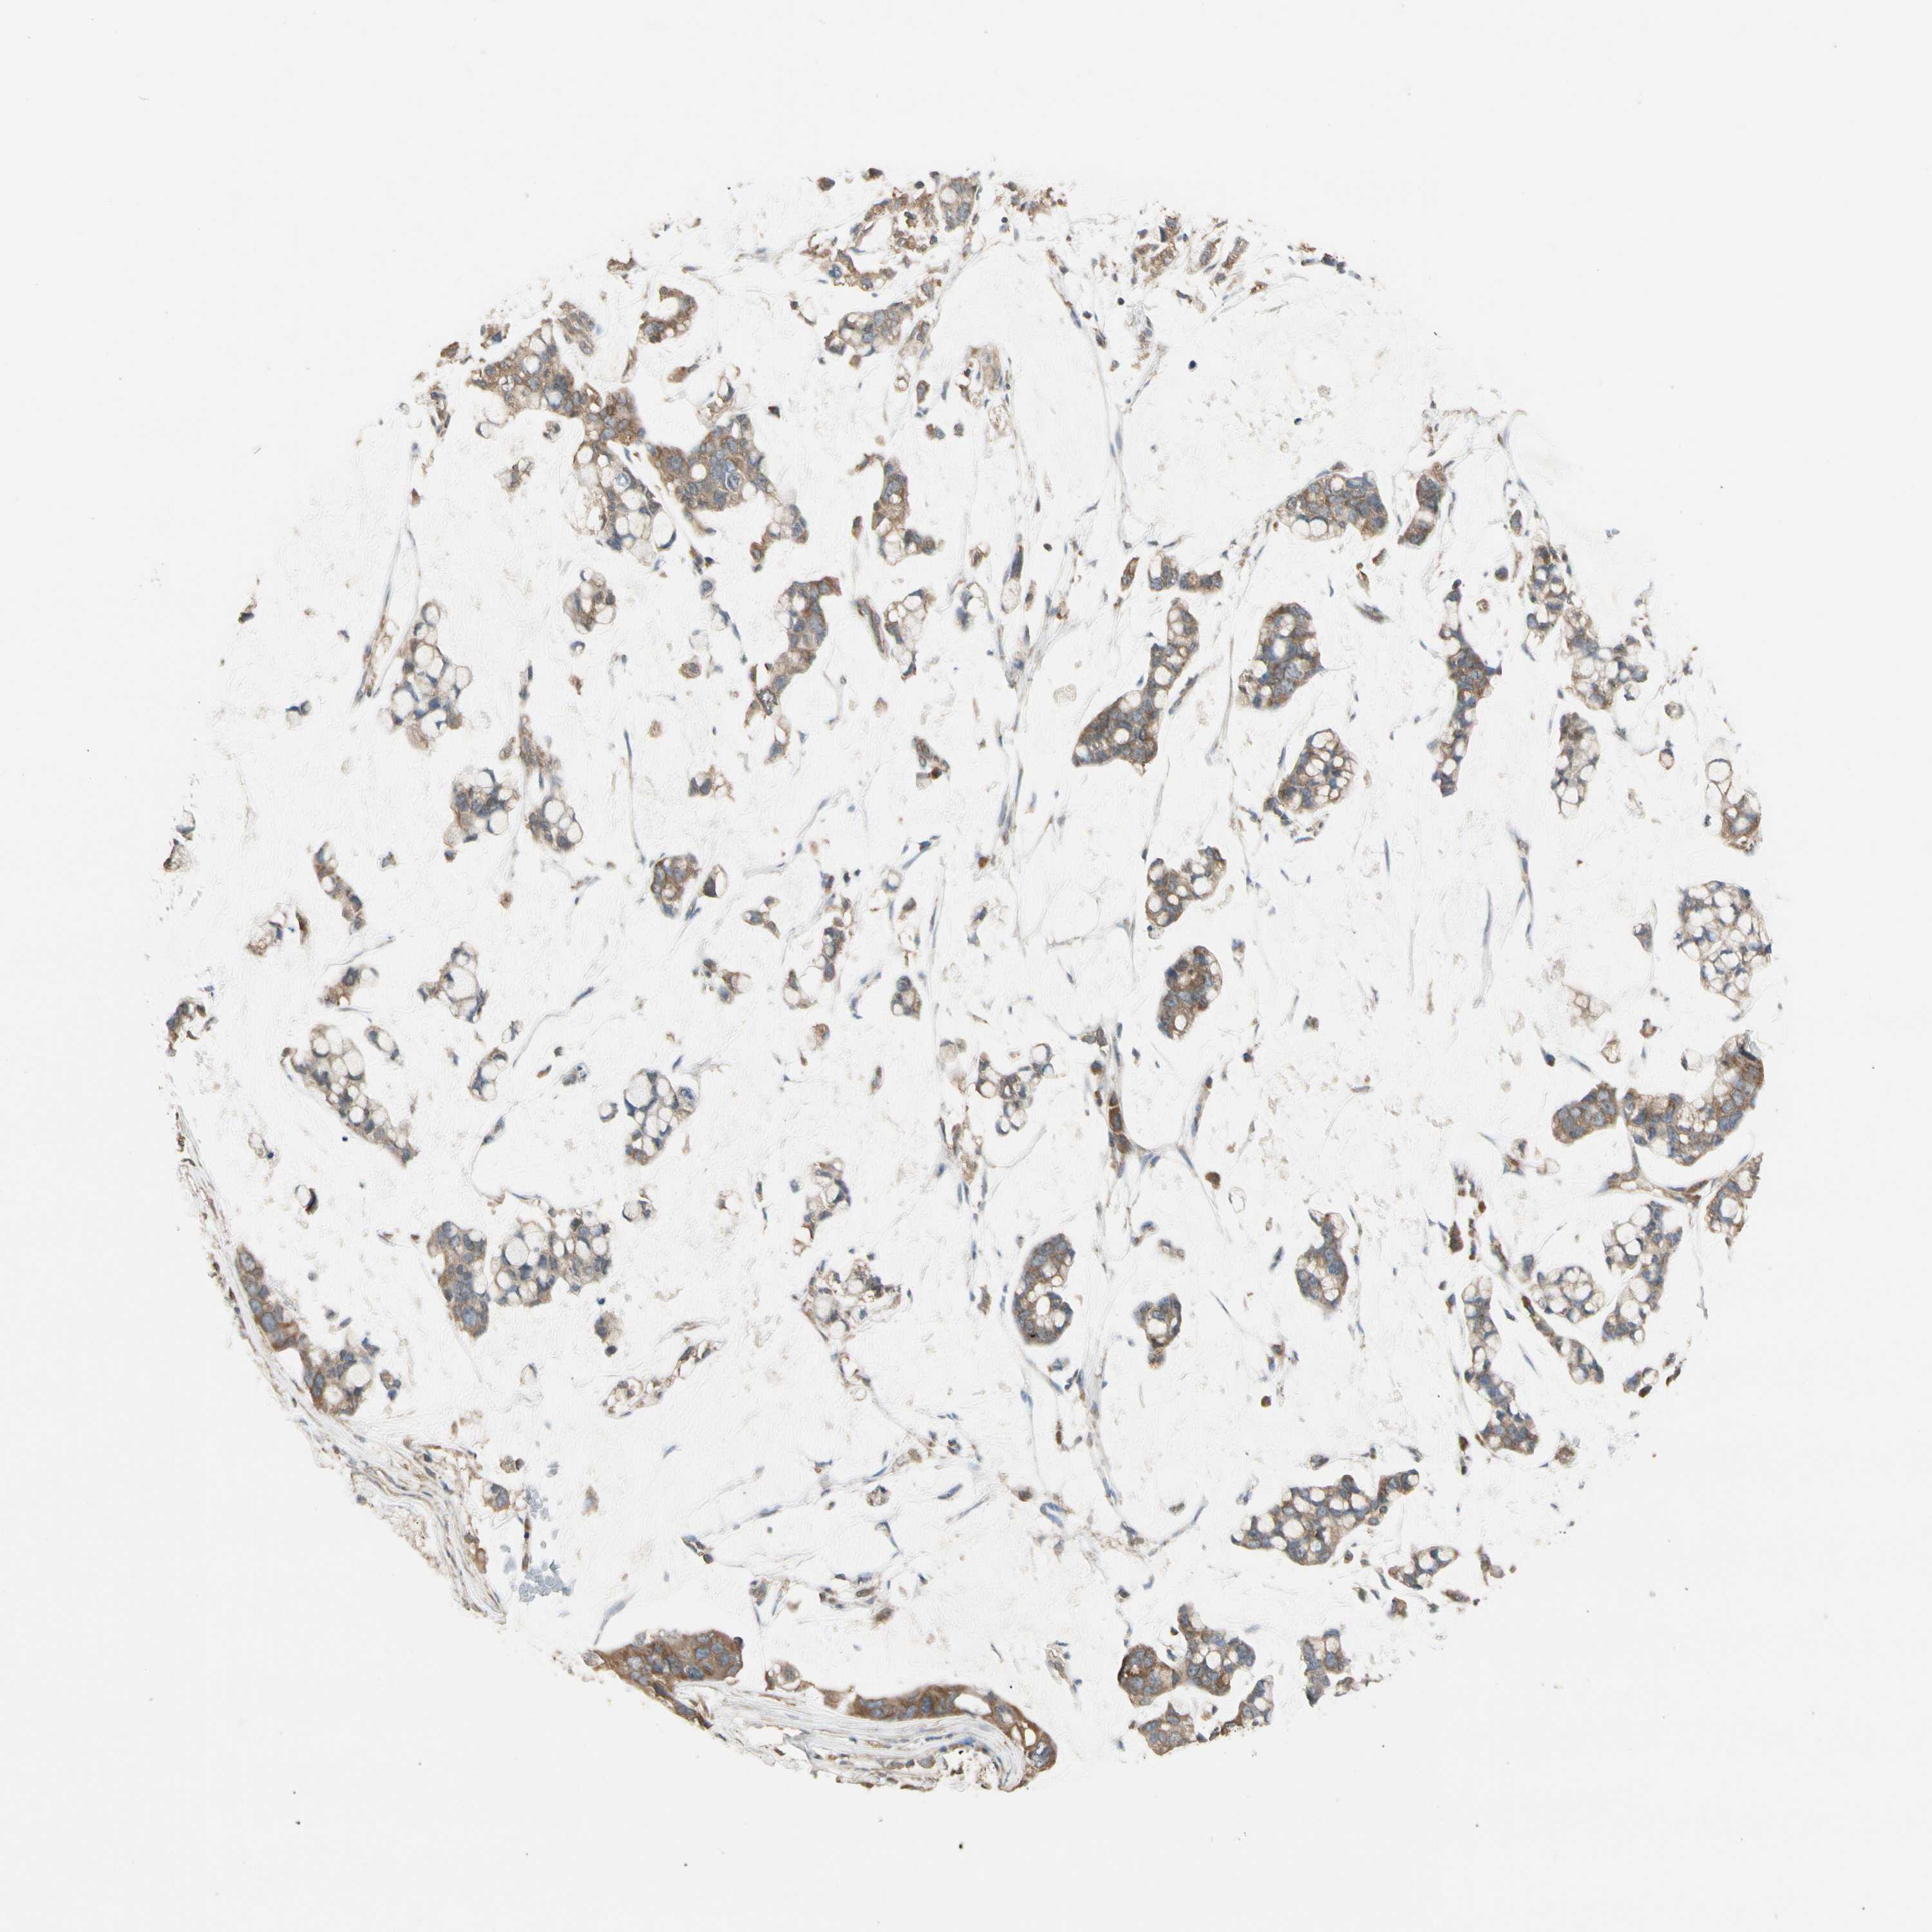

STOMACH CANCER - Protein expressioni

A mouse-over function shows sample information and annotation data. Click on an image to view it in a full screen mode. Samples can be filtered based on level of antibody staining by selecting one or several of the following categories: high, medium, low and not detected. The assay and annotation is described here.

Note that samples used for immunohistochemistry by the Human Protein Atlas do not correspond to samples in the TCGA dataset.

Antibody stainingi

Antibody staining in the annotated cell types in the current human tissue is reported as not detected, low, medium, or high, based on conventional immunohistochemistry profiling in selected tissues. This score is based on the combination of the staining intensity and fraction of stained cells.

Each image is clickable and will lead to virtual microscopy that enables deeper exploration of all samples and also displays staining intensity scores, fraction scores and subcellular localization as well as patient and tissue information for each sample.

Antibody HPA003019

Staining

High

Medium

Low

Not detected

Intensity

Strong

Moderate

Weak

Negative

Quantity

>75%

75%-25%

<25%

None

Location

Nuclear

Cytoplasmic/membranous

Cytoplasmic/membranous,nuclear

Adenocarcinoma, NOS